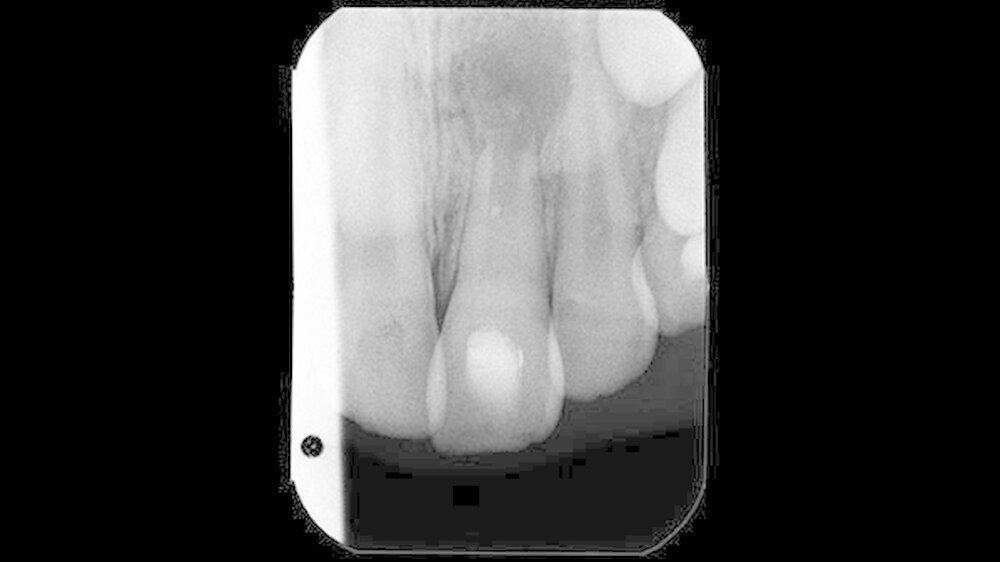

Zwei Jahre später bemerkte der Patient eine dezente Schwellung im Bereich der linken Oberlippe. Unter Schmerzen oder Aufbissempfindlichkeit litt der Patient dabei nicht. In diesem Zustand stellte sich der Patient in der Poliklinik für Zahnerhaltung des Universitätsklinikums Münster erstmals vor. Nach eingehender Anamnese und Befunderhebung wurde eine aktuelle Zahnfilmaufnahme angefertigt (Abbildung 2).

Auf der Zahnfilmaufnahme zeigte der Zahn 21 ein weiterhin nicht abgeschlossenes Wurzelwachstum und eine ausgedehnte apikale Osteolyse. Im Vergleich zur altersentsprechend entwickelten Wurzel des Zahnes 11 erschien die Wurzellänge des traumatisierten Zahnes verkürzt. Auch stellte sich das Lumen des Wurzelkanals im Seitenvergleich vergrößert dar.